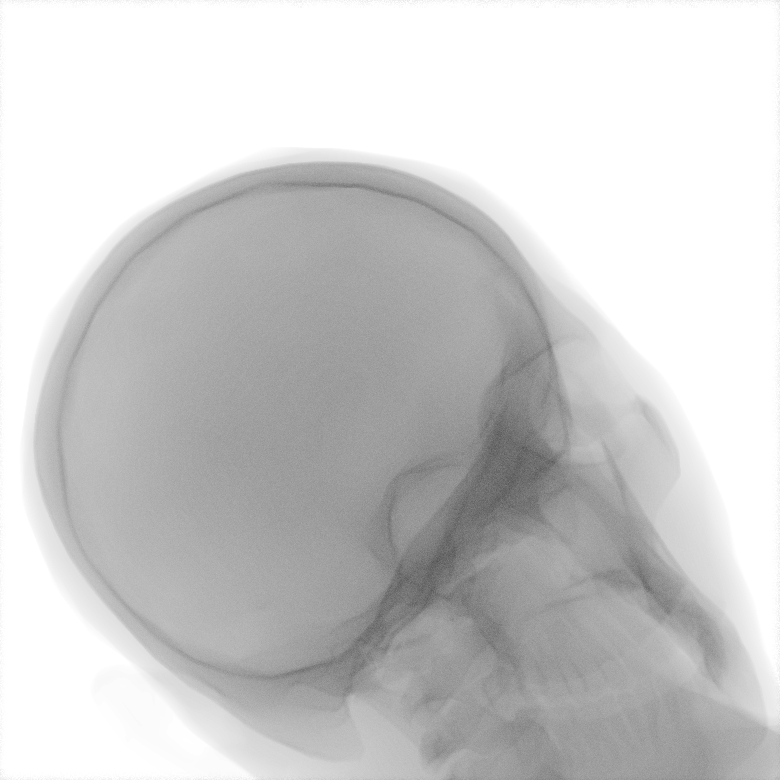

Refer to caption

Figure 2: Dataset overview. The synthetic domain contains Low and High dosage samples generated using the Mentice VIST® simulator; the real domain includes Low, Normal, and Exposure dosage categories acquired from a skull phantom using the Philips Azurion IGT system.

We develop and release a new dataset of real and synthetic head X-ray images, X-DigiSkull, to study the domain adaptation. The dataset consists of synthetic X-ray images of a human skull generated using the Mentice VIST® simulator 111https://www.mentice.com/simulator/vist-g7. Real‑time X‑rays are generated by holding the 3D voxel “patient” head model with per‑voxel attenuation, casting one ray per detector pixel to form a digitally reconstructed radiograph and then approximating scatter, focal‑spot and detector blur, grid/heel effects and detector response, adding quantum/read noise and final image post-processing as the C‑arm and devices move. Real images are acquired from a clinical-grade physical skull phantom using the Philips Azurion Image Guided Therapy (IGT) system. Images are captured from common IGT working positions for neuro procedures. The dataset consists of multiple orientations and is available in three different radiation dose settings: low, normal, and exposure (Philips exclusive), the latter offering enhanced image quality and detail, as shown in Figure 2. This consists of viewing angles rz[40,+40]r_{z}\in[-40^{\circ},+40^{\circ}], ry[40,+40]r_{y}\in[-40^{\circ},+40^{\circ}], rx[40,+40]r_{x}\in[-40^{\circ},+40^{\circ}] with respect to the starting position in 10 increments and up to 3 images at each position to capture the noise present. This results in a total of 2,187 real images. The coordinate systems of the real and synthetic environment are aligned and synthetic images are rendered to approximate the same viewpoints as the real phantom images with the patient table starting at a similar position.The head 3D model used in the simulation is meticulously built from a real clinical case. We capture the synthetic images in finer increments of 5 across the three angles, producing the 5,832 (18318^{3}) images 222Data available at https://zenodo.org/records/16535437. The aim of this alignment is not to achieve precise supervised image translation, but rather to establish a consistent reference structure that preserves spatial features. The composition of the dataset is summarized in Table 1, which contains information on the splits and the number of images available. All images are cropped and resized to 780×\times780 pixels. The test set is obtained by uniformly sampling 15% of viewing angles and corresponding images to ensure a representative distribution. For our experiments, we focus on the task of converting synthetic images at high dose to real images at normal dose.